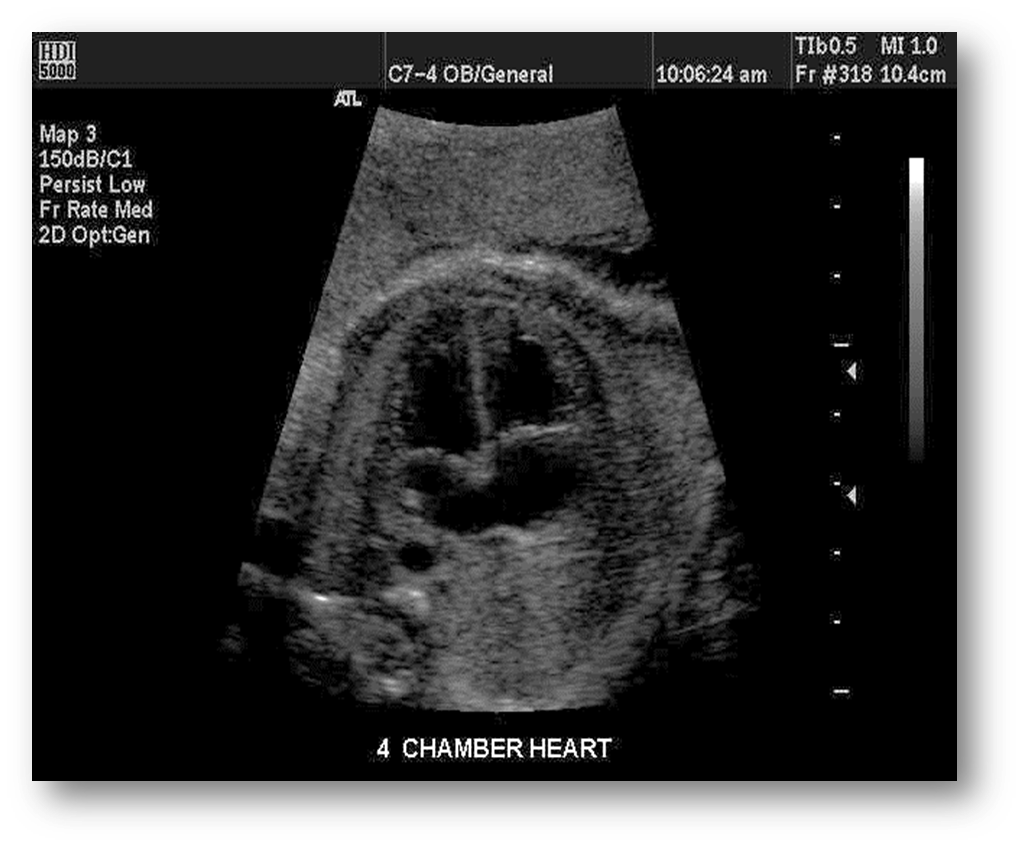

What view is this?

outflow tract

4 chamber view

Normal 4 chamber view